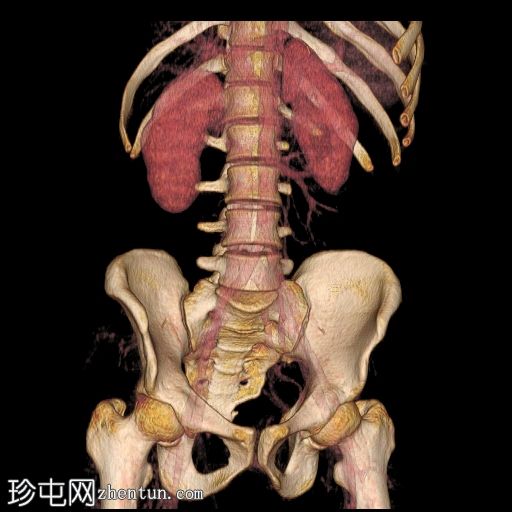

冠状位

血管窗

6.jpg

最大强度投影 (MIP)

7.jpg

本病例展示了一条环绕主动脉的副左肾静脉,其走行于主动脉后方并汇入下腔静脉,而右肾静脉解剖结构正常。

双侧肾动脉解剖结构正常,双侧肾动脉均起源于L2椎体水平的腹主动脉,管径正常,无狭窄、动脉瘤、夹层或副动脉。